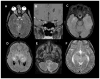

Neurofibromatosis type 1 (NF1) is one of the most common brain tumor predisposition syndromes, in which affected children are prone to the development of low-grade gliomas. While NF1-associated gliomas can be found in several brain regions, the majority arise in the optic nerves, chiasm, tracts, and radiations (optic pathway gliomas; OPGs). Owing to their location, 35-50% of affected children present with reduced visual acuity. Unfortunately, despite tumor stabilization following chemotherapy, vision does not improve in most children. For this reasons, more effective therapies are being sought that reflect a deeper understanding of the NF1 gene and the use of authenticated Nf1 genetically-engineered mouse strains. The implementation of these models for drug discovery and validation has galvanized molecularly-targeted clinical trials in children with NF1-OPG. Future research focused on defining the cellular and molecular factors that underlie optic glioma development and progression also has the potential to provide personalized risk assessment strategies for this pediatric population.